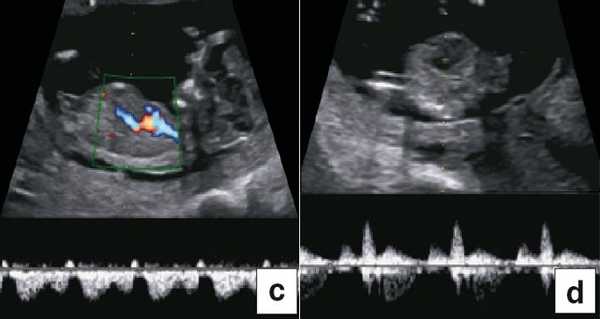

В 90% случаев крупные анеуплоидии у плодов можно обнаружить с помощью комбинированной оценки возраста матери, измерений ТВП и сывороточных маркеров у матери (РАРР-А и свободный бета-ХГЧ) [8]. Результат такого скрининга можно улучшить, исследуя сывороточные маркеры раньше, на сроках от 9 до 10 нед, и проводя УЗИ на 12-й неделе для выявления дополнительных маркеров, таких как носовая кость плода, кровоток в венозном протоке и через трехстворчатый клапан (рис. 5) [9]. Кроме того, выявлять часто встречающиеся хромосомные аномалии у плода позволяет неинвазивное пренатальное тестирование (Non Invasive Prenatal Testing - NIPT).

Рис. 5. Оценка анеуплоидии по ультразвуковым маркерам: толщина воротникового пространства (a), носовая кость (b), венозный проток (c), кровоток через трехстворчатый клапан (d).

В группах с высоким риском развития врожденных пороков сердца (ВПС) эхокардиографию плода можно проводить на ранних сроках. Обычно исследование выполняет специалист, хорошо знакомый с пренатальной диагностикой ВПС. Высокий риск развития ВПС у плода выявляют не только по данным анамнеза пациентки и семейного анамнеза или воздействия токсических факторов, но и по увеличению ТВП и изменению кровотока в венозном протоке и через трехстворчатый клапан [9]. "Подробную" эхокардиографию плода обычно проводят только в группе высокого риска, а проводить "базовую" эхокардиографию в общей популяции в настоящее время не рекомендовано.

Тем не менее "базовое" УЗИ обычно дополняют исследованием в цветовом энергетическом допплеровском режиме с тщательным анализом для выявления атриовентрикулярного кровотока в четырех камерах сердца (рис. 6a) и в срезе через три сосуда и трахею (рис. 6b). Получив эти срезы, обычно можно успокоить родителей, исключив наличие тяжелых пороков сердца, таких как единственный желудочек, гипоплазия желудочков, полный дефект предсердно-желудочковой перегородки (atrioventricular septal defect - AVSD), атрезия аорты или легочной артерии, а также ряд аномалий расположения артерий.

Рис. 6. Эхокардиография плода на ранних сроках в цветовом энергетическом допплеровском режиме - визуализируются четыре камеры (a) и срез через три сосуда и трахею (b).